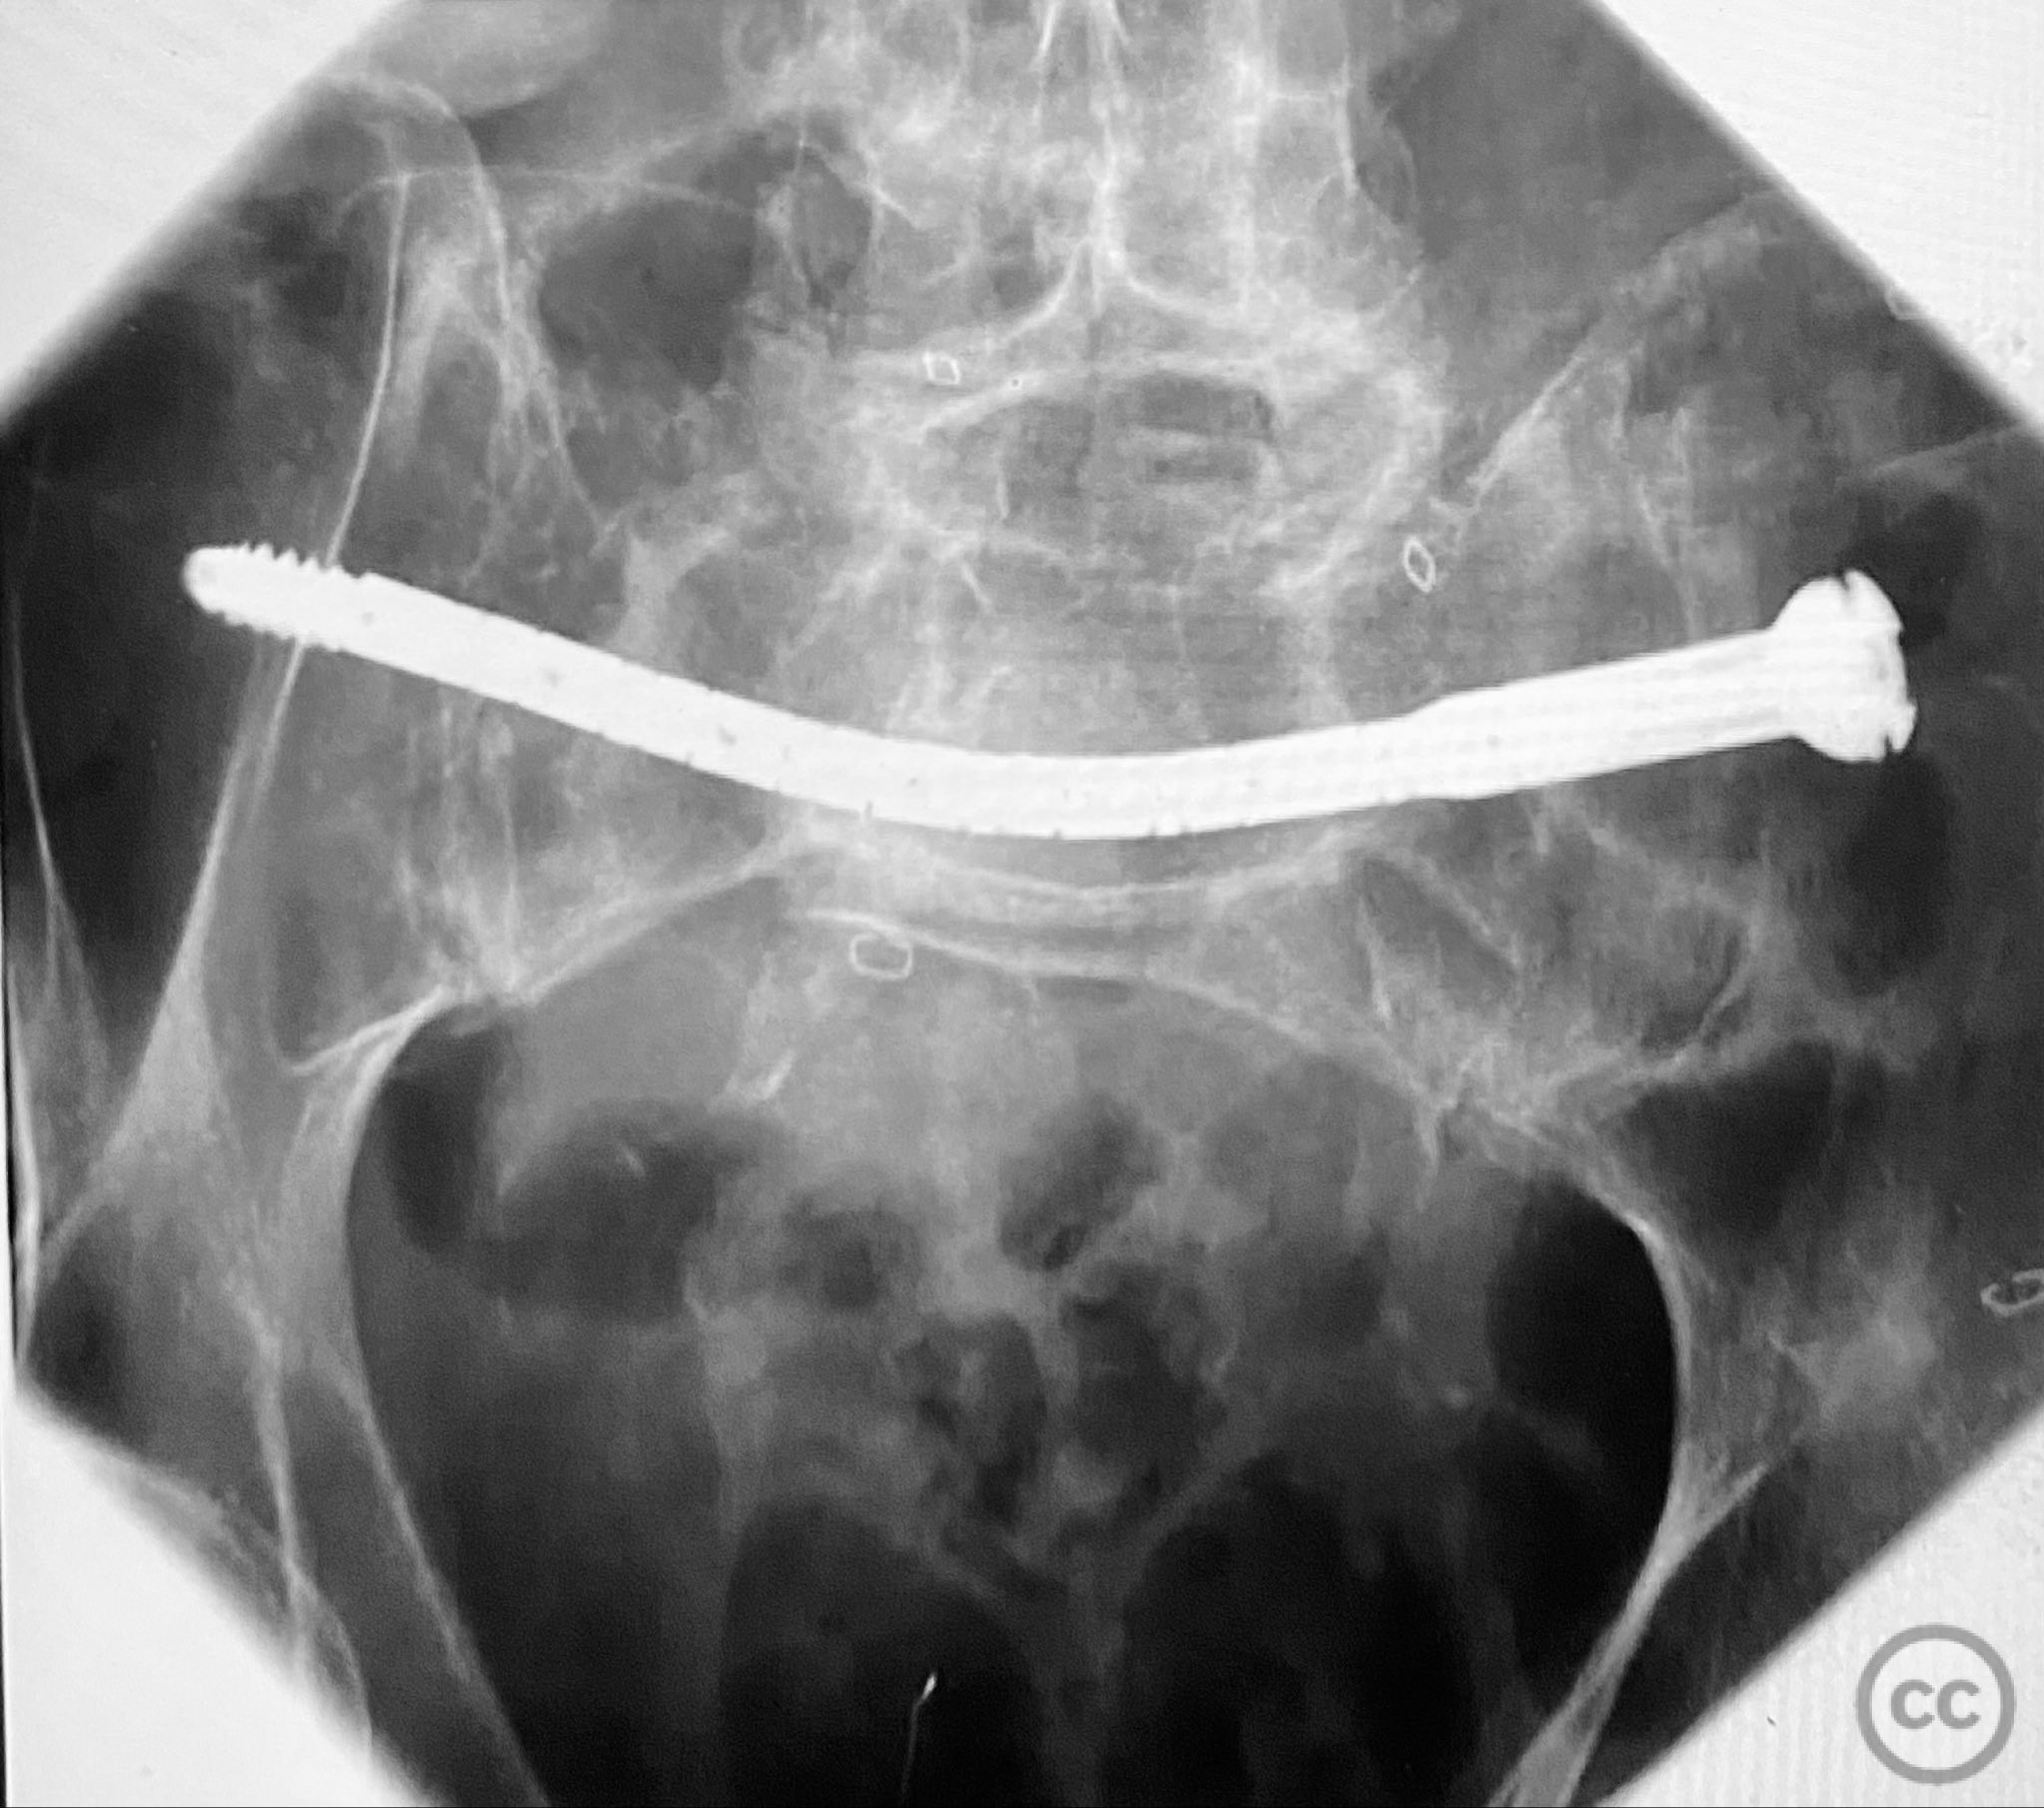

Planning remarks:  The preoperative plan involved percutaneous stabilization of the bilateral oblique upper sacral fractures using a cannulated, articulated intramedullary fixation device (CurvaFix). The anatomical approach was planned to accommodate the oblique trajectory of the sacral fracture pathways, with bilateral guide pin placement under fluoroscopic guidance, followed by device insertion and locking.

Patient positioning:  The patient was positioned supine on a radiolucent operating table to facilitate fluoroscopic imaging in multiple planes (anteroposterior, inlet, and outlet views) for accurate guide pin and device placement.

Anatomical surgical approach:  Percutaneous access was established over the dorsal aspect of the pelvis. Small incisions were made lateral to the sacrum, and soft tissue dissection was performed to the level of the os sacrum. Guide pins were advanced under fluoroscopic control along the oblique upper sacral corridors bilaterally. The cannulated CurvaFix device was inserted over each guide pin, articulated to match the oblique fracture pathway, and subsequently locked in situ according to the manufacturer’s specifications.

The articulated nature of the CurvaFix device allowed precise accommodation of the complex oblique upper sacral fracture pathways bilaterally. Percutaneous technique minimized soft tissue disruption and surgical morbidity. Postoperative CT imaging confirmed satisfactory device placement and fracture reduction. The achieved stability provided immediate pain relief, reduced or eliminated narcotic requirements, and enabled early mobilization. Surgeons with experience in device removal have reported no technical difficulties.